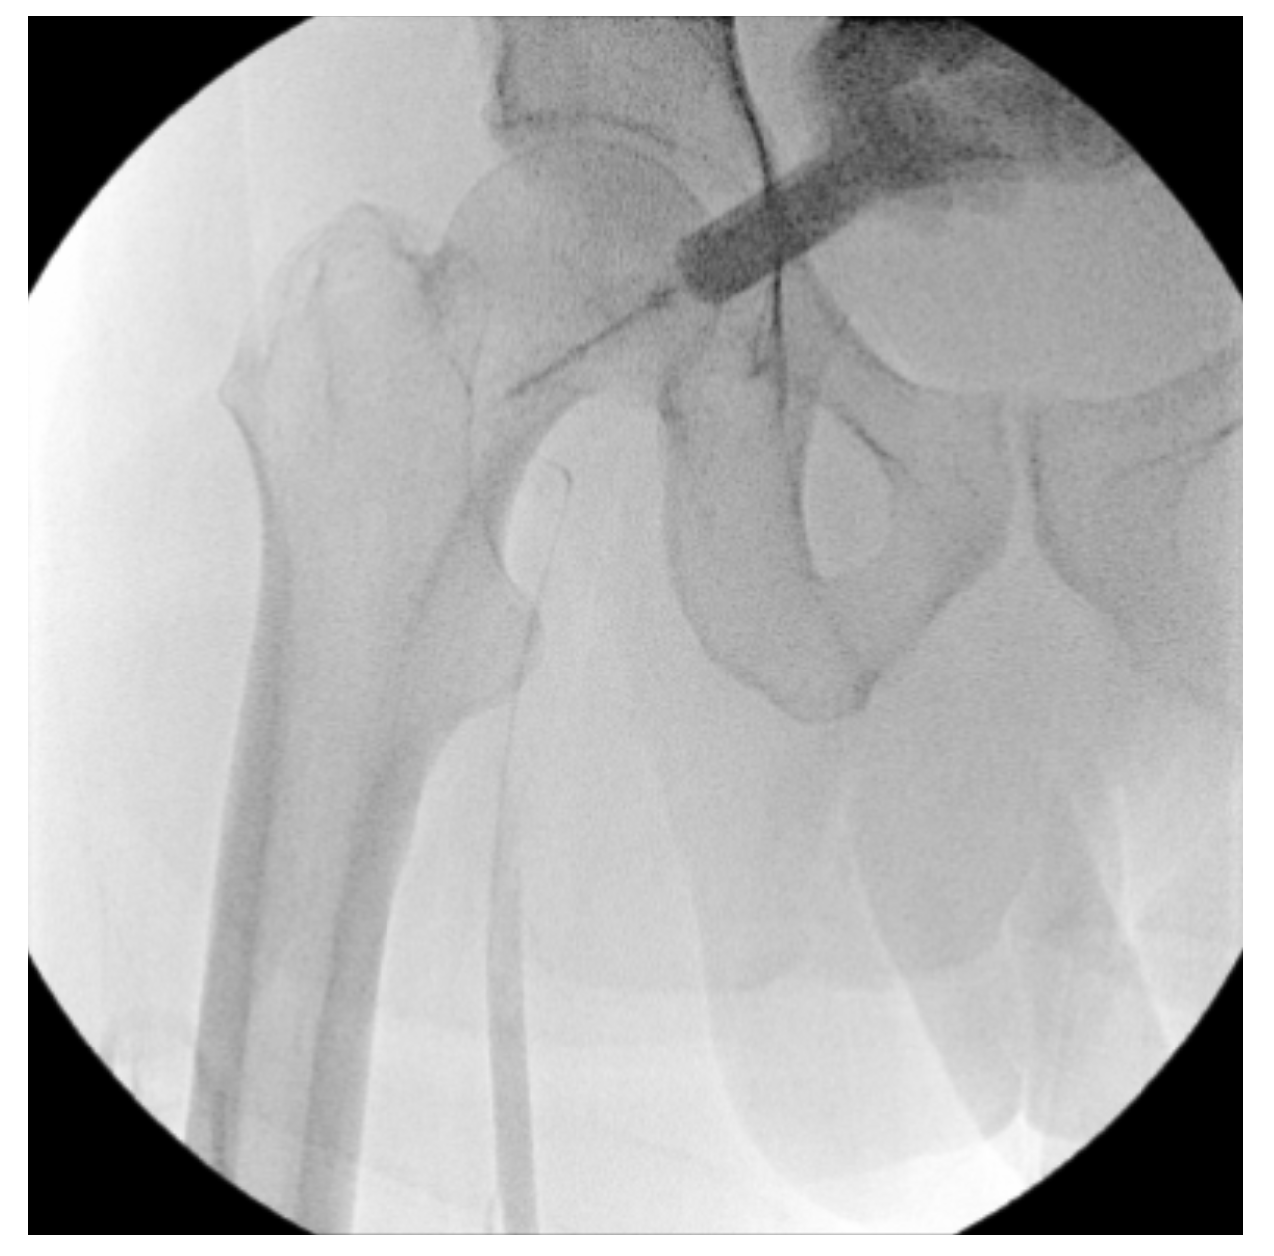

A right lower-extremity angiogram was performed using ultrasound guidance for antegrade access of the proximal superficial femoral artery (Figure 2A). Fluoroscopic acquisition demonstrated no significant disease in the superficial femoral artery (Figure 2B) and popliteal artery (Figure 2C), with no significant stenosis seen in the anterior tibial artery, PTA, and peroneal artery (Figure 2D). Pedal angiography demonstrated a complete pedal-plantar loop formed by the DPA and the lateral plantar artery (LPA) (Figure 2F).